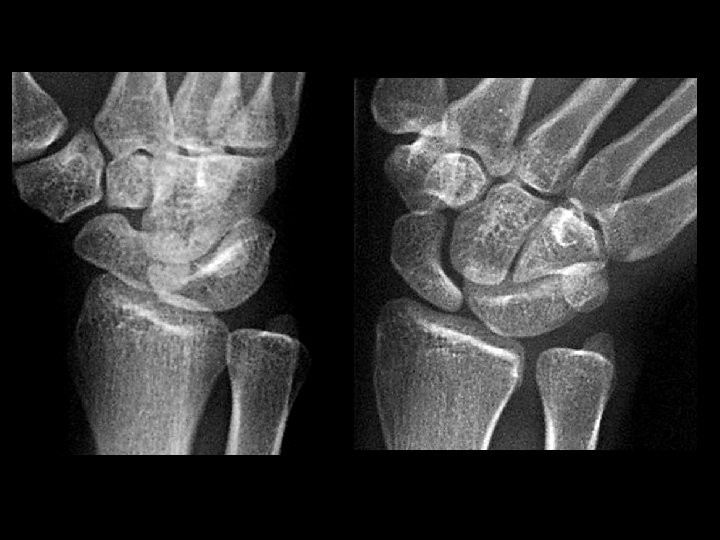

Trans-scaphoid perilunate dislocation • Findings: – Fracture of the radial styloid, scaphoid, and ulnar styloid – Posterior dislocation of the capitellum • ddx: – NONE! – This is an Aunt Minnie!

Lunate dislocation • Findings: – Disruption of proximal carpal row – “Pie-shaped lunate” – Lateral view is diagnostic • ddx: – NONE! – This is an Aunt Minnie!